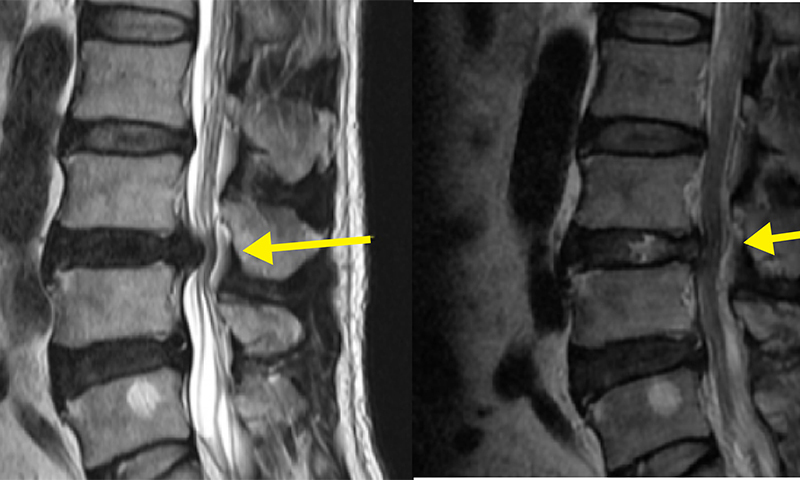

허리디스크는 추간판, 즉 척추 뼈 사이의 연골조직이 제자리에서 밀려나 신경을 압박하면서 허리와 다리에 통증을 유발하는 질환이다. 초기에는 허리통증이나 엉치통증 정도로 시작되지만, 점차 증상이 심해지면 다리 저림이나 감각 이상, 심한 경우 대소변 장애까지 초래할 수 있다.

서울바른세상병원 신경외과 전문의 배장호 원장에 따르면 최소침습 디스크 제거술은 국소마취 하에 1cm 미만의 절개를 통해 특수 카메라와 장비를 삽입한 뒤, 신경을 압박하고 있는 디스크 조각만을 정밀하게 제거하는 수술이다.